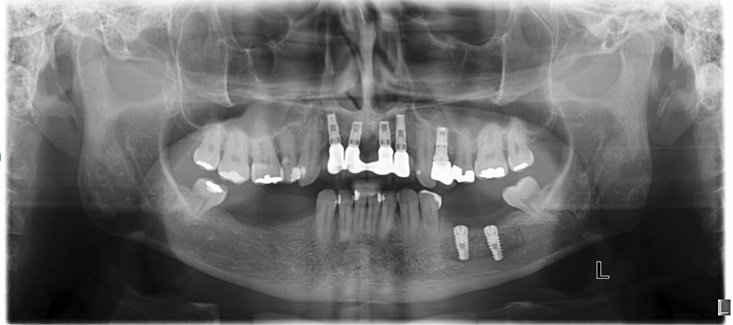

A colocação de implantes na parte posterior da mandíbula esta geralmente limitada pela altura do osso entre o canal do nervo alveolar e a crista óssea do nervo alveolar.

Depois de fazermos um planejamento detalhado na tomografia e modelo de estudo ou protótipos da mandíbula obtidos através da tomografia computadorizada, como tamanho e numero dos implantes, confeccionamos um guia cirúrgico em acrílico e marcando com precisão a localização dos implantes a serem instalados. Fig. 1 e 2

Sutura feita com vicryl 4-0 e raio-x pós-cirúrgico.